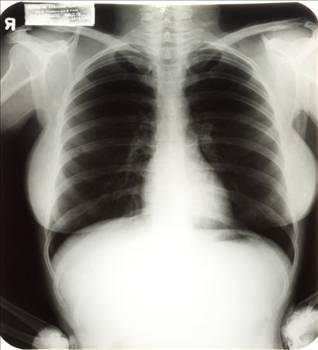

Marilyn Monroe'nun akciğer filmi de satılacak

Marilyn Monroe'nun 1954'te çekilen akciğer filmi önümüzdeki günlerde bir açık arttırmada satılacak. Monroe'nun doktoru ameliyat öncesi çektiği bu filmi kızına bırakmıştı ve kızı da bu filmi yaklaşık 1.200 dolara açık arttırmada satmayı düşünüyor

Monroe'nun açık artırmaya çıkan diğer bir eşyası ise terapi koltuğu. Koltuğu, monroe'nun psikoloğu Dr. Ralph Greenson açık artırmaya çıkarmıştı.